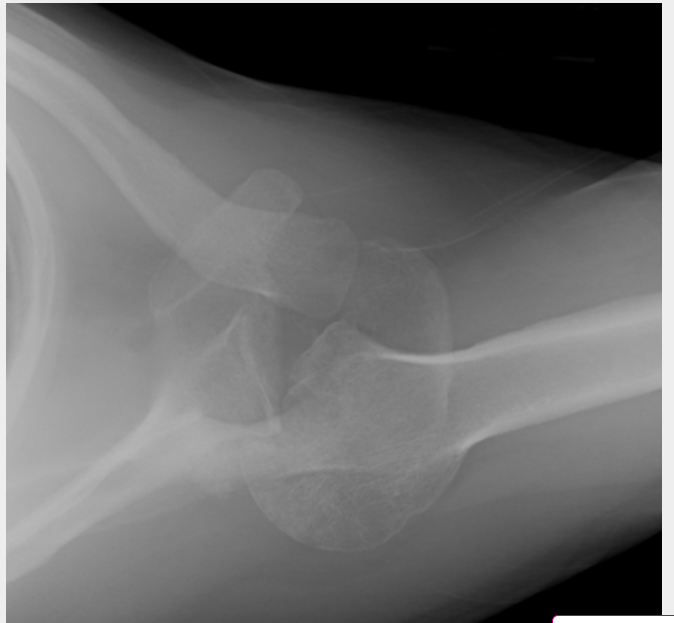

Axillary lateral of a shoulder with a missed posterior dislocation: humeral head clearly is not reduced and is locked on the posterior rim of the glenoid